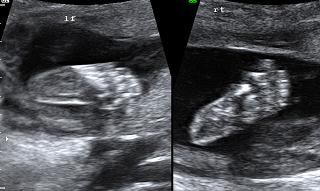

• 香港结构超声波照片

香港结构超声波照片

结构性超声波, 四维 香港, 四维结构性超声波 结构性超声波, 四维 结构性超声波, 四维 香港, 四维结构性超声波 结构性超声波, 四维 香港, 四维结构性超声波 结构性超声波, 四维 结构性超声波, 四维 结构性超声波, 四维 香港, 四维结构性超声波 结构性超声波, 四维 香港, 四维结构性超声波 结构性超声波, 四维 结构性超声波, 四维